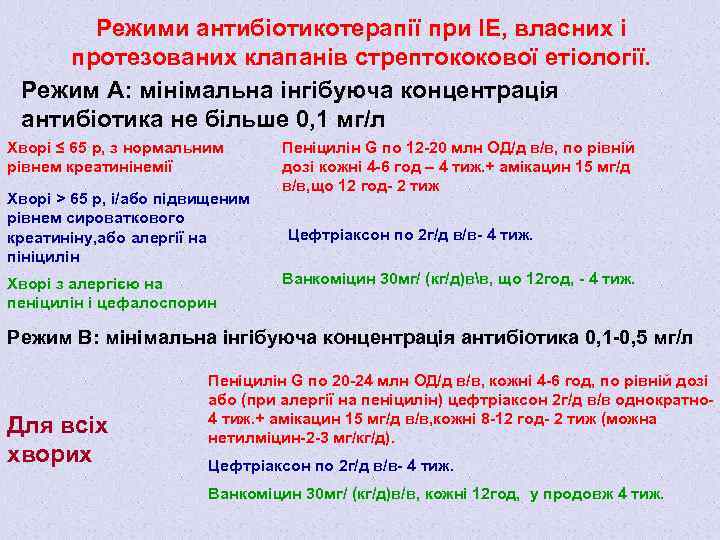

Режими антибіотикотерапії при ІЕ, власних і протезованих клапанів стрептококової етіології. Режим А: мінімальна інгібуюча концентрація антибіотика не більше 0, 1 мг/л Хворі ≤ 65 р, з нормальним рівнем креатинінемії Хворі > 65 р, і/або підвищеним рівнем сироваткового креатиніну, або алергії на пініцилін Хворі з алергією на пеніцилін і цефалоспорин Пеніцилін G по 12 -20 млн ОД/д в/в, по рівній дозі кожні 4 -6 год – 4 тиж. + амікацин 15 мг/д в/в, що 12 год- 2 тиж Цефтріаксон по 2 г/д в/в- 4 тиж. Ванкоміцин 30 мг/ (кг/д)вв, що 12 год, - 4 тиж. Режим В: мінімальна інгібуюча концентрація антибіотика 0, 1 -0, 5 мг/л Для всіх хворих Пеніцилін G по 20 -24 млн ОД/д в/в, кожні 4 -6 год, по рівній дозі або (при алергії на пеніцилін) цефтріаксон 2 г/д в/в однократно 4 тиж. + амікацин 15 мг/д в/в, кожні 8 -12 год- 2 тиж (можна нетилміцин-2 -3 мг/кг/д). Цефтріаксон по 2 г/д в/в- 4 тиж. Ванкоміцин 30 мг/ (кг/д)в/в, кожні 12 год, у продовж 4 тиж.